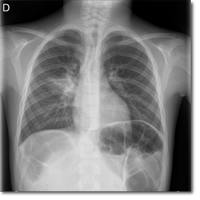

Varón de dos años y siete meses que es llevado a Urgencias por fiebre de 48 horas de evolución,...

Zafra Anta MA, Pérez Segura MdP, Nombela Fernández G.

11 febrero 2014